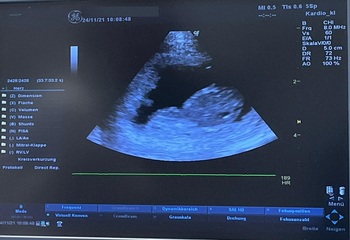

Ultraschallbild, 24.11.2021